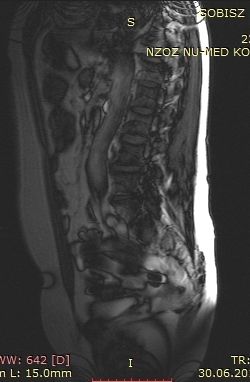

Chciałbym aby ktoś opisał mi zdjęcia z rezonansu kręgosłupa lędżwiowego jestem po 3 operacjach kręgozmyku miałem diam ktury się rozerwał potem jakiś inny implat ktury się obluzował teraz go wyjeli i co dalej.sorry za błędy....